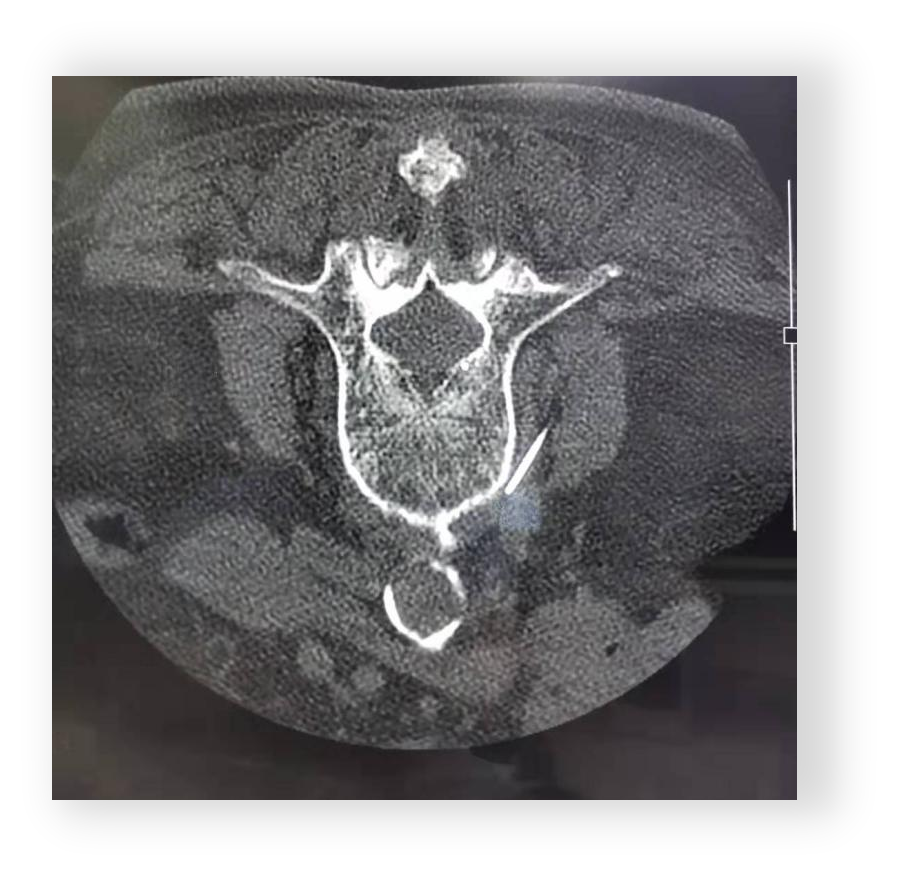

髋关节CT(2024-07-19):双侧髋关节退行性变。